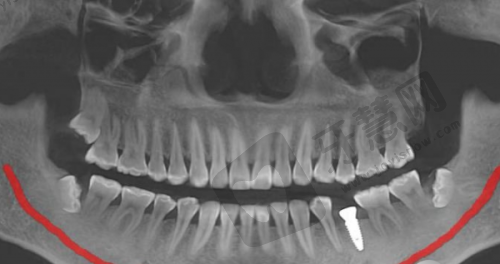

了解沧州莱恩口腔门诊部提供的服务特色,帮助您做出更明智的选择。莱恩口腔门诊部提供多种口腔医疗服务,包括口腔身体科、外科、正畸和儿童口腔等。医院的医生团队经验丰富,特别是在种植牙和儿童正畸领域,医生张岩和何小妹分别在这方面有着十年以上的从业经验,能够为患者提供个性化的治疗方案。医院还配备了先进的医疗设备,如全景CT和数字化种植中心,确保每位患者都能享受到高质量的口腔医疗服务。